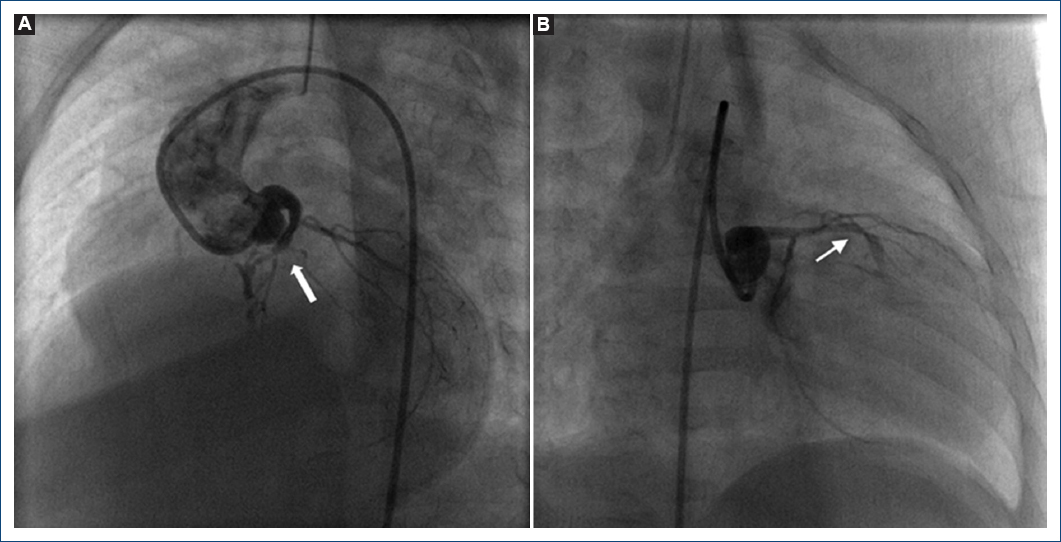

Paciente de sexo femenino de tres meses de edad, peso 4.0 kg, talla 54 cm. Cianosis desde el tercer día de vida, referida por sospecha de cardiopatía congénita. A la exploración física con cianosis ++, soplo continuo infraclavicular izquierdo II/IV. ECOTT: AP-SVI, VD hipoplásico, válvula tricúspide pequeña, ramas pulmonares confluentes de buen calibre, CIA de derecha a izquierda con gradiente máximo de 3 mmHg, CAP con estenosis a su llegada a la arteria pulmonar. Cateterismo cardiaco: presenta crisis de hipoxia y se coloca un stent coronario no medicado 4 x 16 mm en el conducto arterioso, con lo que mejora su saturación; se confirmó CCVDD de manera inadvertida al cruzar la válvula tricúspide y generar insuficiencia tricuspídea moderada (Fig. 5), en este momento presentó bradicardia, infradesnivel en el segmento S-T. Se logra realizar una ventriculografía derecha confirmándose la AP-SVI y las CVC, se retira el catéter y paulatinamente se logra estabilidad hemodinámica en aproximadamente 15 minutos, se realiza coronariografía izquierda que demuestra atresia de la DA en su tercio medio (Fig. 6), se decide no realizar septotomía atrial, evoluciona de manera favorable con EKG sin datos de lesión ni de infarto (Fig. 7) y se egresa a las 48 horas. Diecinueve meses después presenta de manera súbita irritabilidad por unos segundos, presenta pérdida del estado de alerta y fallece en domicilio. No se realiza estudio post mortem.

Figura 5 Ventriculografía derecha proyección postero-anterior. A: se observa atresia pulmonar con septum ventricular íntegro con conexiones ventrículo-coronarias con insuficiencia tricuspídea generada por el catéter angiográfico (flecha). B: al retirar el catéter angiográfico desparece la insuficiencia tricuspídea.